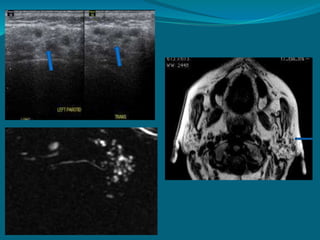

MRI revealing lymphoepithelial

cyst involving right parotid

MR sialography

 MRI with evoked

salivation.

 Lemon juice – stimulate

 Reveal ductal morphology

accurately ,sialolith

identification

 Alternative to conventional

sialography.